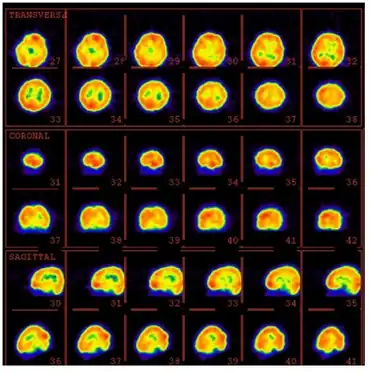

99mTc-ECD brain perfusion SPECT image of an individual with Landau-Kleffner syndrome

The most effective way of confirming LKS is by obtaining overnight sleep EEGs, including EEGs in all stages of sleep. Many conditions like demyelination and brain tumors can be ruled out by using magnetic resonance imaging (MRI). In LKS, fluorodeoxyglucose (FDG) and positron emission tomography (PET) scanning can show decreased metabolism in one or both temporal lobes - hypermetabolism has been seen in patients with acquired epileptic aphasia.[5]